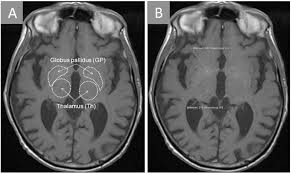

Classified as a lanthanide, gadolinium is a solid at room temperature. Gbcas are generally thought to be safe to use in patients with good kidney function. The use of gadolinium contrast dyes during pregnancy has been linked to rheumatological, inflammatory and infiltrative skin conditions. Your provider believes that an mri scan will help doctors diagnose your health condition. Gadolinium contrast media (sometimes called a mri contrast media, agents or 'dyes') are chemical substances used in magnetic resonance imaging (mri) scans. The gadolinium levels are also similar across. Routine screening and laboratory testing for renal failure is no longer required prior to the administration of group ii agents. Gbca) for magnetic resonance imaging and computer tomography scanning. It is a strong magnet at room temperature. Establishing the gadolinium toxicity connection symptoms are generally experienced at an acute level shortly after having a contrast mri and at a chronic level for years following their last contrast mri. A landmark research article released in 2016 by semelka et al. The side effects patients are reporting now include joint pain, muscle fatigue and cognitive impairment that can last for years. Gadolinium contrast is also called an mri medium, agent or dye.

Gadolinium oxide (gd2 o 3) is a ceramic compound that has two possible structures, a more stable cubic one, and a monoclinic structure that is achieved when the cubic structure reaches 1200°c. Gadolinium contrast media (sometimes called a mri contrast media, agents or 'dyes') are chemical substances used in magnetic resonance imaging (mri) scans. But gadolinium in gbcas goes through a process called chelation, which makes it safer for use in the body. Gadolinium has atomic number 64 on the periodic table. Gadolinium was discovered in 1880 and isolated in 1886.

The gadolinium used in the dye is anchored to a molecule to create a nontoxic compound. Indications and usage for dotarem. Proposed the name gadolinium deposition disease for a disease process seen in patients who had normal or near normal function of the kidney but who still developed persistent symptoms of gadolinium toxicity hours to months after these contrast agents were used on them. But gadolinium in gbcas goes through a process called chelation, which makes it safer for use in the body. What is gadolinium contrast medium? There are multiple gadolinium contrast agents used, including gadoterate meglumine, gadobenate dimegluamine, gadodiamide, gadopentate, gadoversetamide, gadobutrol, gadoxetate and others. Serious but rare side effects such as gadolinium toxicity and nephrogenic systemic fibrosis, or nsf, are most often seen in patients with severe kidney problems. 3.0 out of 5 stars.